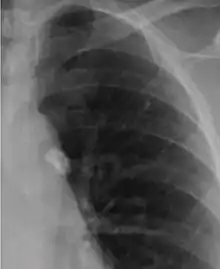

It is a small area of granulomatous inflammation, only detectable by chest X-ray if it calcifies or grows substantially (see tuberculosis radiology).[2] Typically these will heal, but in some cases, especially in immunosuppressed patients, it will progress to miliary tuberculosis (so named due to the granulomas resembling millet seeds on a chest X-ray).[2]

The classical location for primary infection is surrounding the lobar fissures, either in the upper part of the lower lobe or lower part of the upper lobe.[2]

Ghon focus.